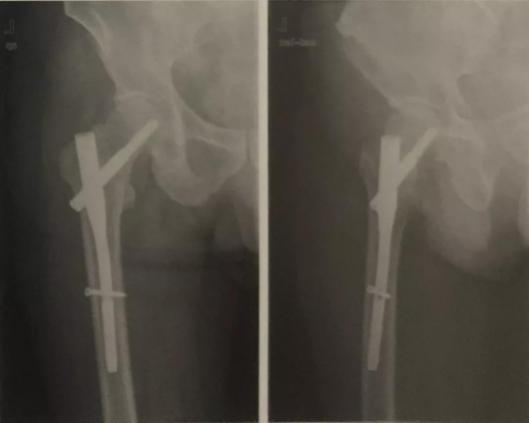

再次,您的手術(shù)需要固定嗎?骨折一般需要使用內(nèi)、外固定器械對骨折端進行固定,骨科常用的固定器材有鋼板、螺釘、髓內(nèi)釘、外固定架等種類繁多,而不同部位的骨折,不一樣的骨折形態(tài)所需的固定器械又不盡相同,這就需要醫(yī)生們制定詳細的手術(shù)方案,充分考慮術(shù)前、術(shù)中、術(shù)后可能發(fā)生的各種突發(fā)情況,挑選出最適合病人的固定器械,這也是原因之一。